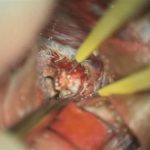

'19年5月

右中小脳脚 出血再発

SM 3(S1,E1,V1)

米国の病院

No.359 モニタリング

No.359 手術前

No.359 手術中

No.359 手術後

出血既往があり。2回の手術前血管内手術の後に、

Lateral transpeduncular approachにより再々出血予防を目的に

摘出手術を行う。完全摘出であることを確認した。

手術による合併症や後遺症なしで退院した。経過良好。